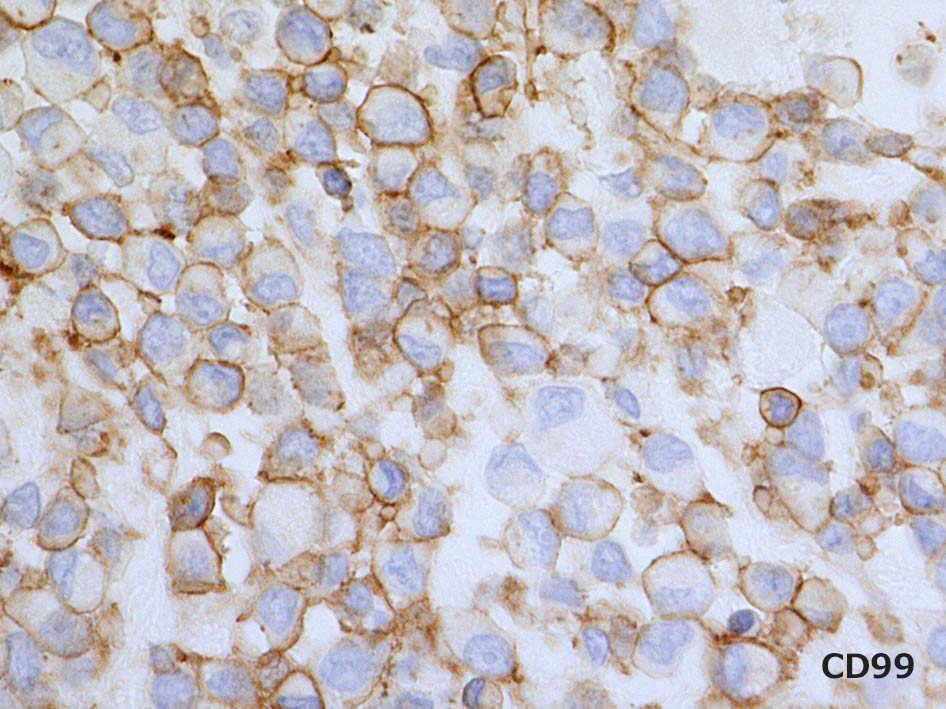

軽鎖がわずかに陽性となり, 最初 plasmacytomaとDxされたが他のmyeloma marker陰性, light chain PCRはnon-clonalパターンであった.追加の免染で, vimentin, CD99(MIC2)陽性、CD34, BCL2がごく一部に陽性など分化不明の肉腫.

Vimentin, CD99(MIC2)はびまん性に陽性を示す. CD34はfocalに陽性. 異型 spindle cellにも陽性を呈する. EMAは少数の陽性細胞あり. BCL2はリンパ球に陽性. 腫瘍細胞はほぼ陰性. 淡く染まる細胞がごく少数ある. CK(AE1/3)は陰性. p53はびまん性, 80%に陽性. (photo準備中). MIB-1 LIは>90%.